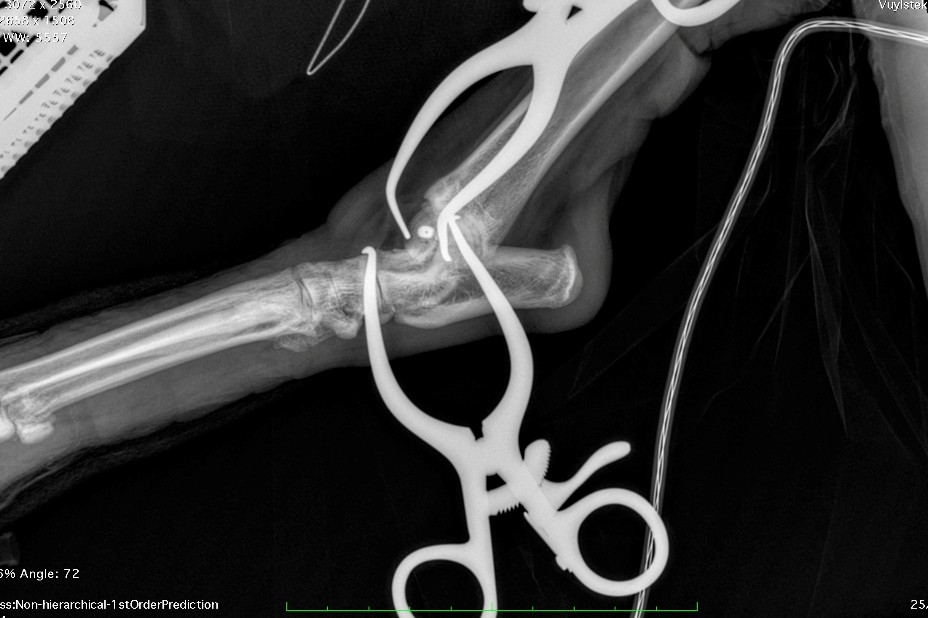

The fracture’s small size, delicate location, and proximity to the joint meant precision was critical. To ensure accurate screw placement, Mark performed the surgery under real-time intra-operative imaging—a technique he has refined over more than a decade. Using continuous X-ray guidance allowed confirmation of ideal screw trajectory and depth, avoiding both joint violation and inadequate fracture engagement.

Instead, Mark and the team opted for an innovative solution: a headless compression screw (HCS), commonly used in human orthopaedic surgery for peri-articular fractures. The HCS generates compression along the fracture line thanks to its differential thread pitch, while its headless design allows full burial within the bone—eliminating the risk of joint interference.